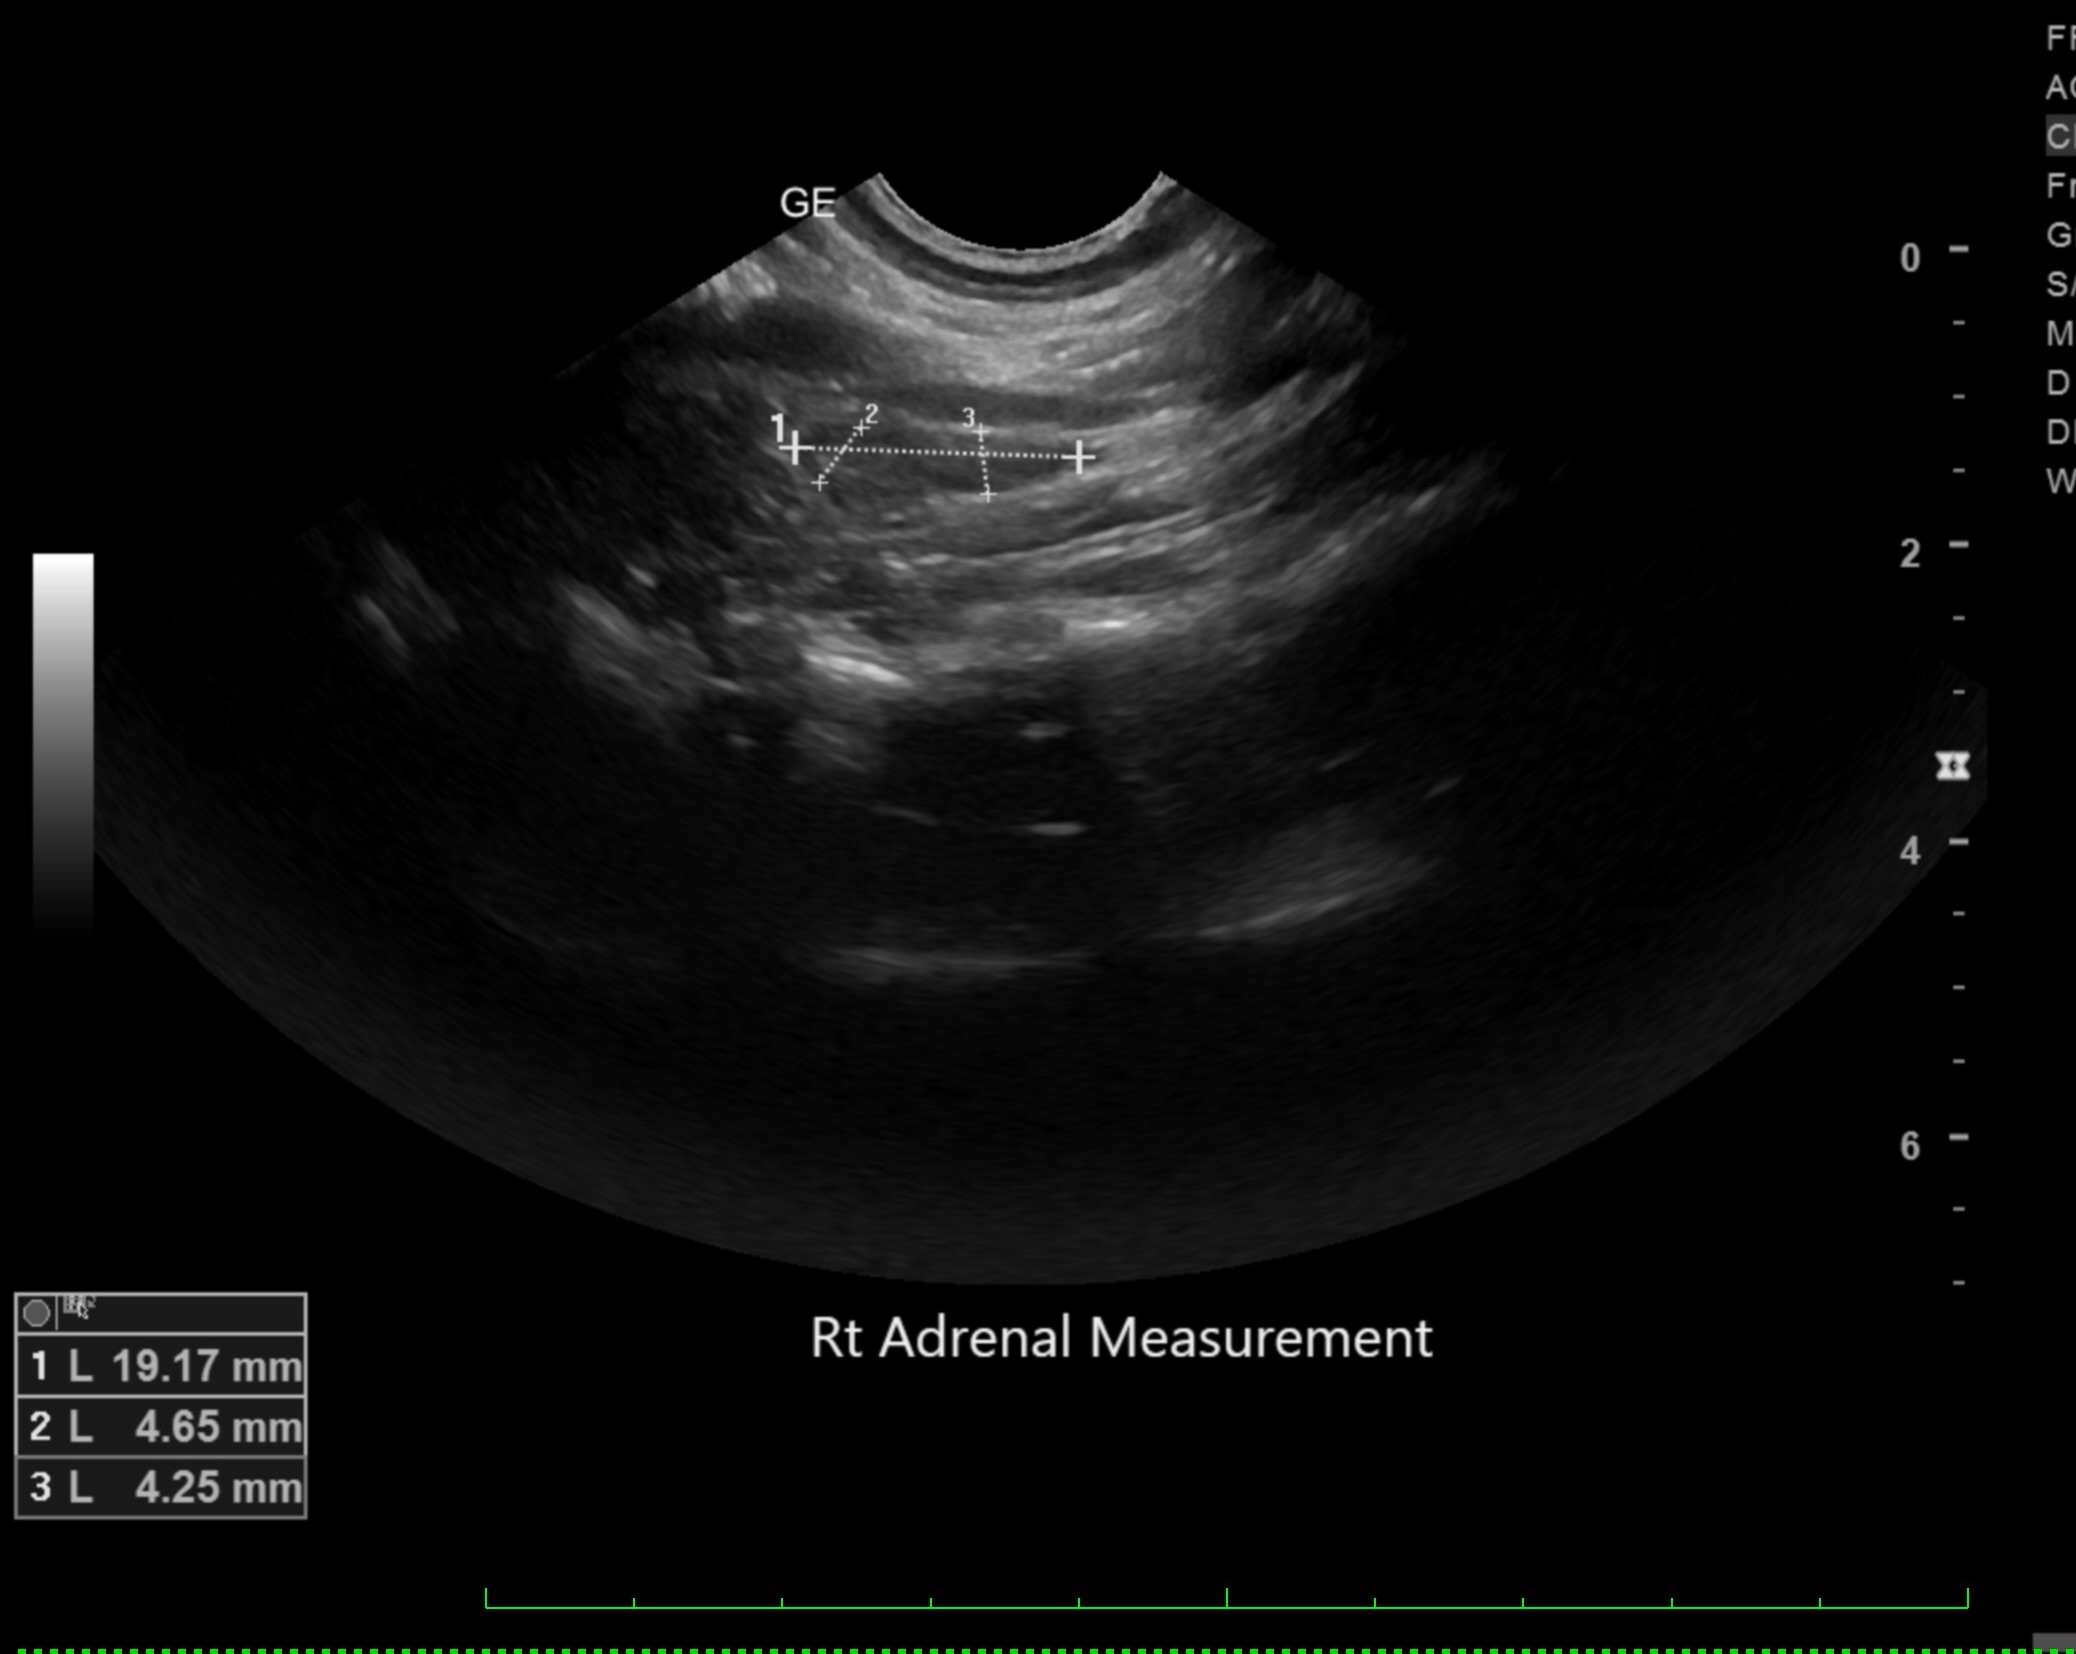

Labwork (fasted): TP 4.5, Alb 2.5, ALP 144, ALT 155, GGT 3, Bili 0.4, Cre 0.3, Cho 51, Amy 266 CBC – HCT 39%, Hgb 12.0 UA – USG 1.030pH 6, 1+ bilirubin, WBC 4-10/hpf, rods 26-50/hpf Negative Accuplex Bile Acids: Pre 299.2, Post-meal – 90.7